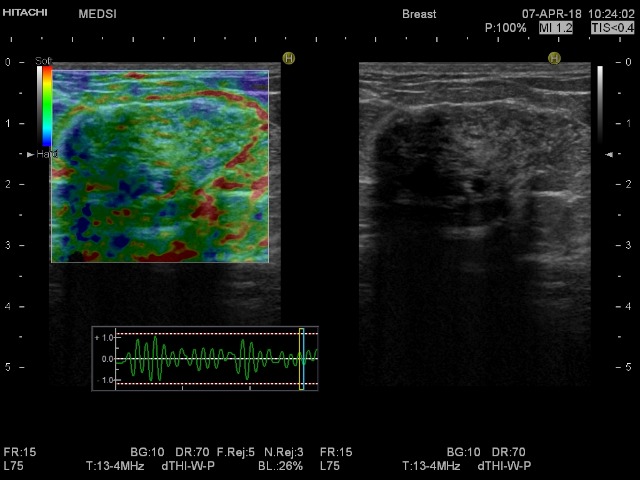

Интрамаммарный ЛУ не может быть.

Intramammary lymphe node

Не , не похоже. Контуры, локализация, структура и дистальные эффекты против л/у. Байрадсом не ругаюсь, но с коллегами согласна.

Конечно, это не интрамаммарный ЛУ. Но о нем вспомнил предыдущий комментатор. Правда, непонятно, какой смысл он вложил в свою фразу "Интрамаммарный ЛУ не может быть", ведь ещё не было речи о таком узле. На всякий случай, я разместил сонограмму интрамаммарного л/узла из атласа, чтобы было с чем сравнить.